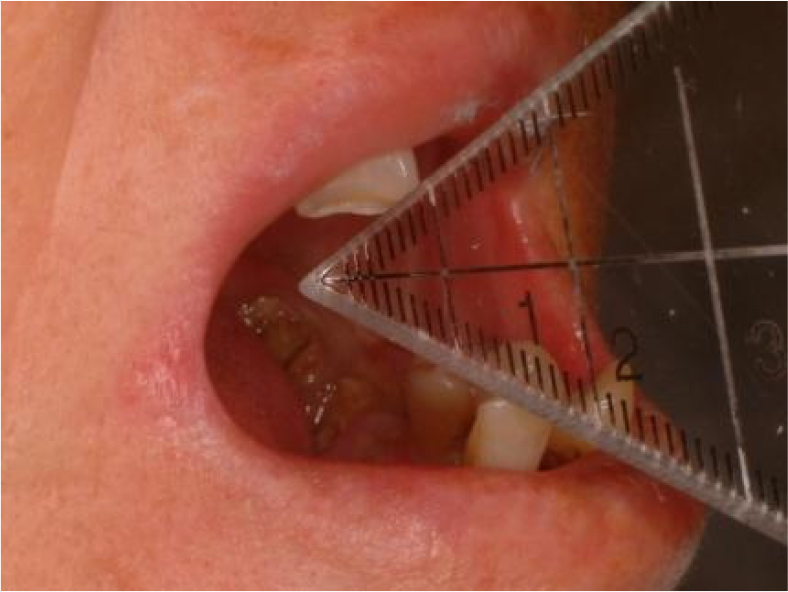

When the patient presented to the Department of Oral and Maxillofacial Surgery, an initial panoramic radiograph revealed multiple retained root tips and missing teeth (Fig. 1). The patient was unable to maintain good oral hygiene because of limited mouth opening. Extra-oral examination revealed a 12-mm mouth opening and facial asymmetry with an anterior crossbite due to maxillary deficiency (Figs. 2 and 3A, 3B, respectively). Underdevelopment of the maxilla was associated with muscle contracture from the previous free flap. Intraoral examination revealed multiple missing teeth, retained roots, and loss of the buccal vestibule.